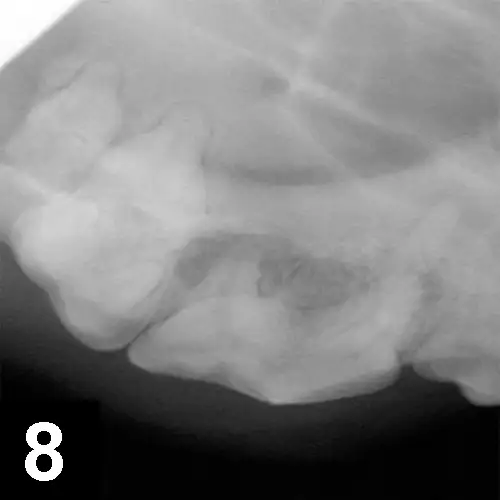

4. Maxillary draining tracts

A maxillary extraoral draining tract rostral to the eye is most commonly associated with chronic infection (periodontal or endodontic) of a maxillary premolar or molar tooth (Figure 6). In brachycephalic breeds, it might even be the canine tooth. Dental disease is subgingival, and both periodontal and endodontic infections can result in maxillary draining tracts. There may be associated bone proliferation or reaction, and the region may be firm on palpation. Dental disease should be the top differential for these lesions before dermatologic conditions, ophthalmologic conditions, or tumors are considered. The infected tooth can be identified with general anesthesia, oral examination, periodontal probing, and intraoral radiographs of the maxillary regional dentition on the ipsilateral side of the draining tract (Figures 7 and 8) with similar radiographs of the contralateral side for comparison. Surgical extraction of the infected tooth or teeth is often necessary. The carnassial tooth is not always at fault; therefore, intraoral radiographs are needed to diagnose the infected tooth, which could be any of the ipsilateral dentition (eg, first maxillary molar).